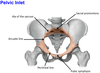

Where are the 3 potential sites of obstruction of the ureters in case of kidney stones?

- at the junction of the ureters and the renal pelvis

- where the ureters cross the brim of the pelvic inlet

- during their passage through the wall of the bladder